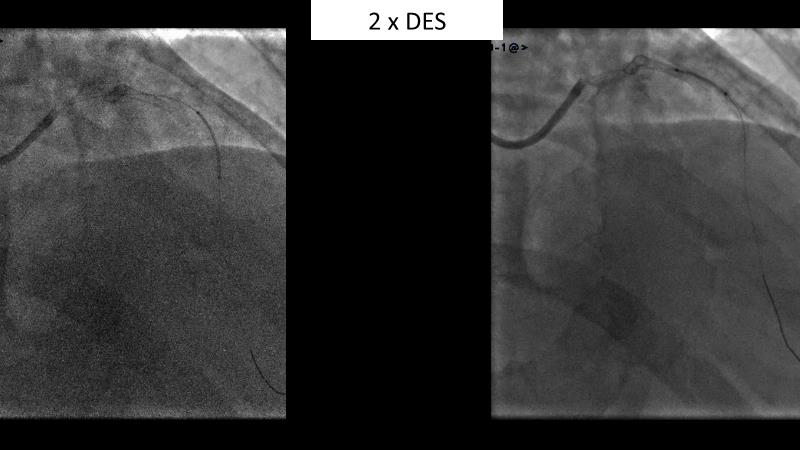

Watch this session to gain case-based insights on using DCBs in complex settings. Learn valuable tips and tricks for optimal DCB application, including the best timing and situations for their use. Discover how to effectively implement a hybrid strategy that combines DES and DCB when needed.

- To get a case based experience on how to use a DCB in complex settings

- To utilise the hybrid strategy approach Combining DES and DCB when the situation demands